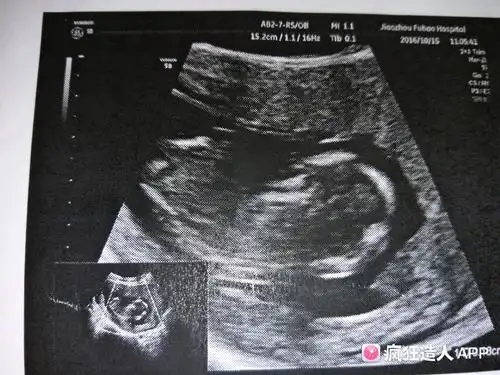

13周nt 今天秒过,宝宝前几天都不配合,老是坐着,今天给妈妈争气了.

正常nt厚度应小于3mm